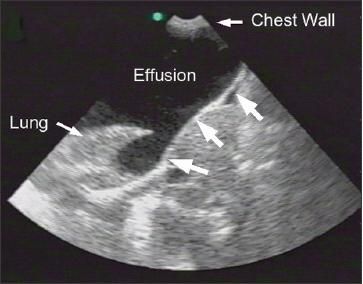

The boundaries of a pleural effusion are defined by the identification of organs adjacent to the effusion- in particular, the liver, spleen, heart, and lung (Figure 1). The lung adjacent to a pleural effusion may be atelectatic, consolidated, or aerated. An aerated lung can be visualized only indirectly by the typical air artifacts, such as comet tails, or total reflection of the ultrasound beam with obscuration of underlying structures.

Figure 1 –

This anechoic pleural effusion is contained within the defining anatomic boundaries, such as the lung, chest wall, and diaphragm (large arrows).